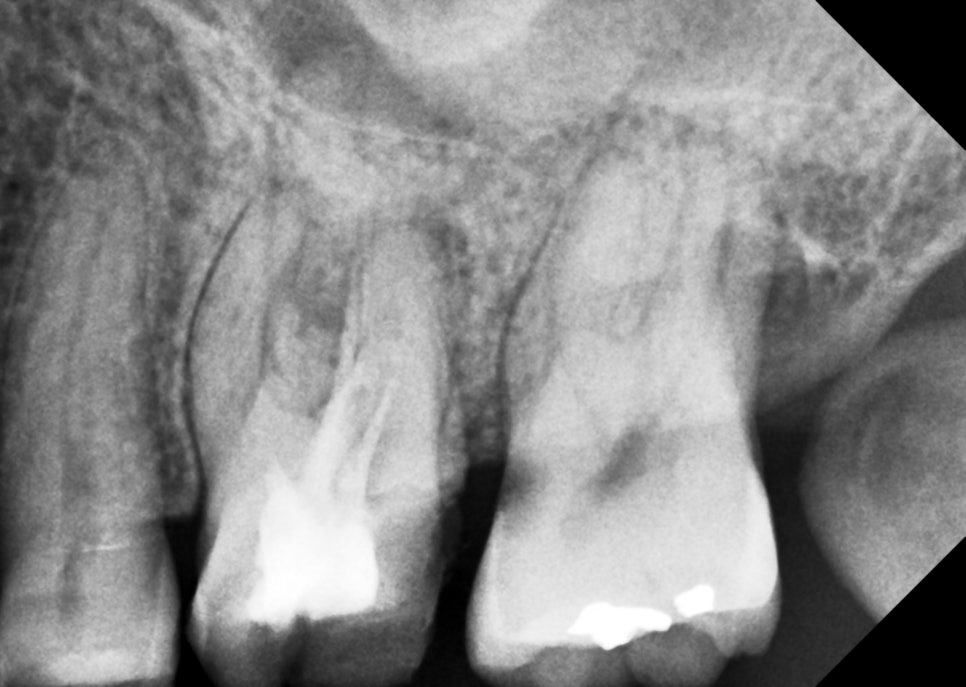

MB2 발견

그 전에 진료하신 원장님이 못 찾은

숨겨진 근관도 하나 더 찾았다.

치아 하나에 신경관이 참 많다.